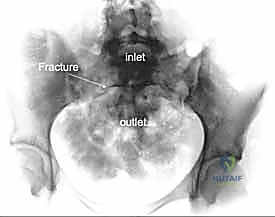

2. الأشعة السينية (X-rays): توفر نظرة أولية سريعة على كسور الحوض (AP, Inlet, and Outlet views).